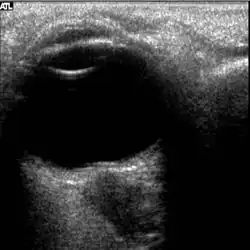

Figure 5: On-orbit ultrasound of posterior orbit of the fourth case of visual changes from long-duration spaceflight. In-flight ultrasound image of the right eye showing posterior globe flattening and a raised optic disc consistent with optic-disc edema and raised ICP.